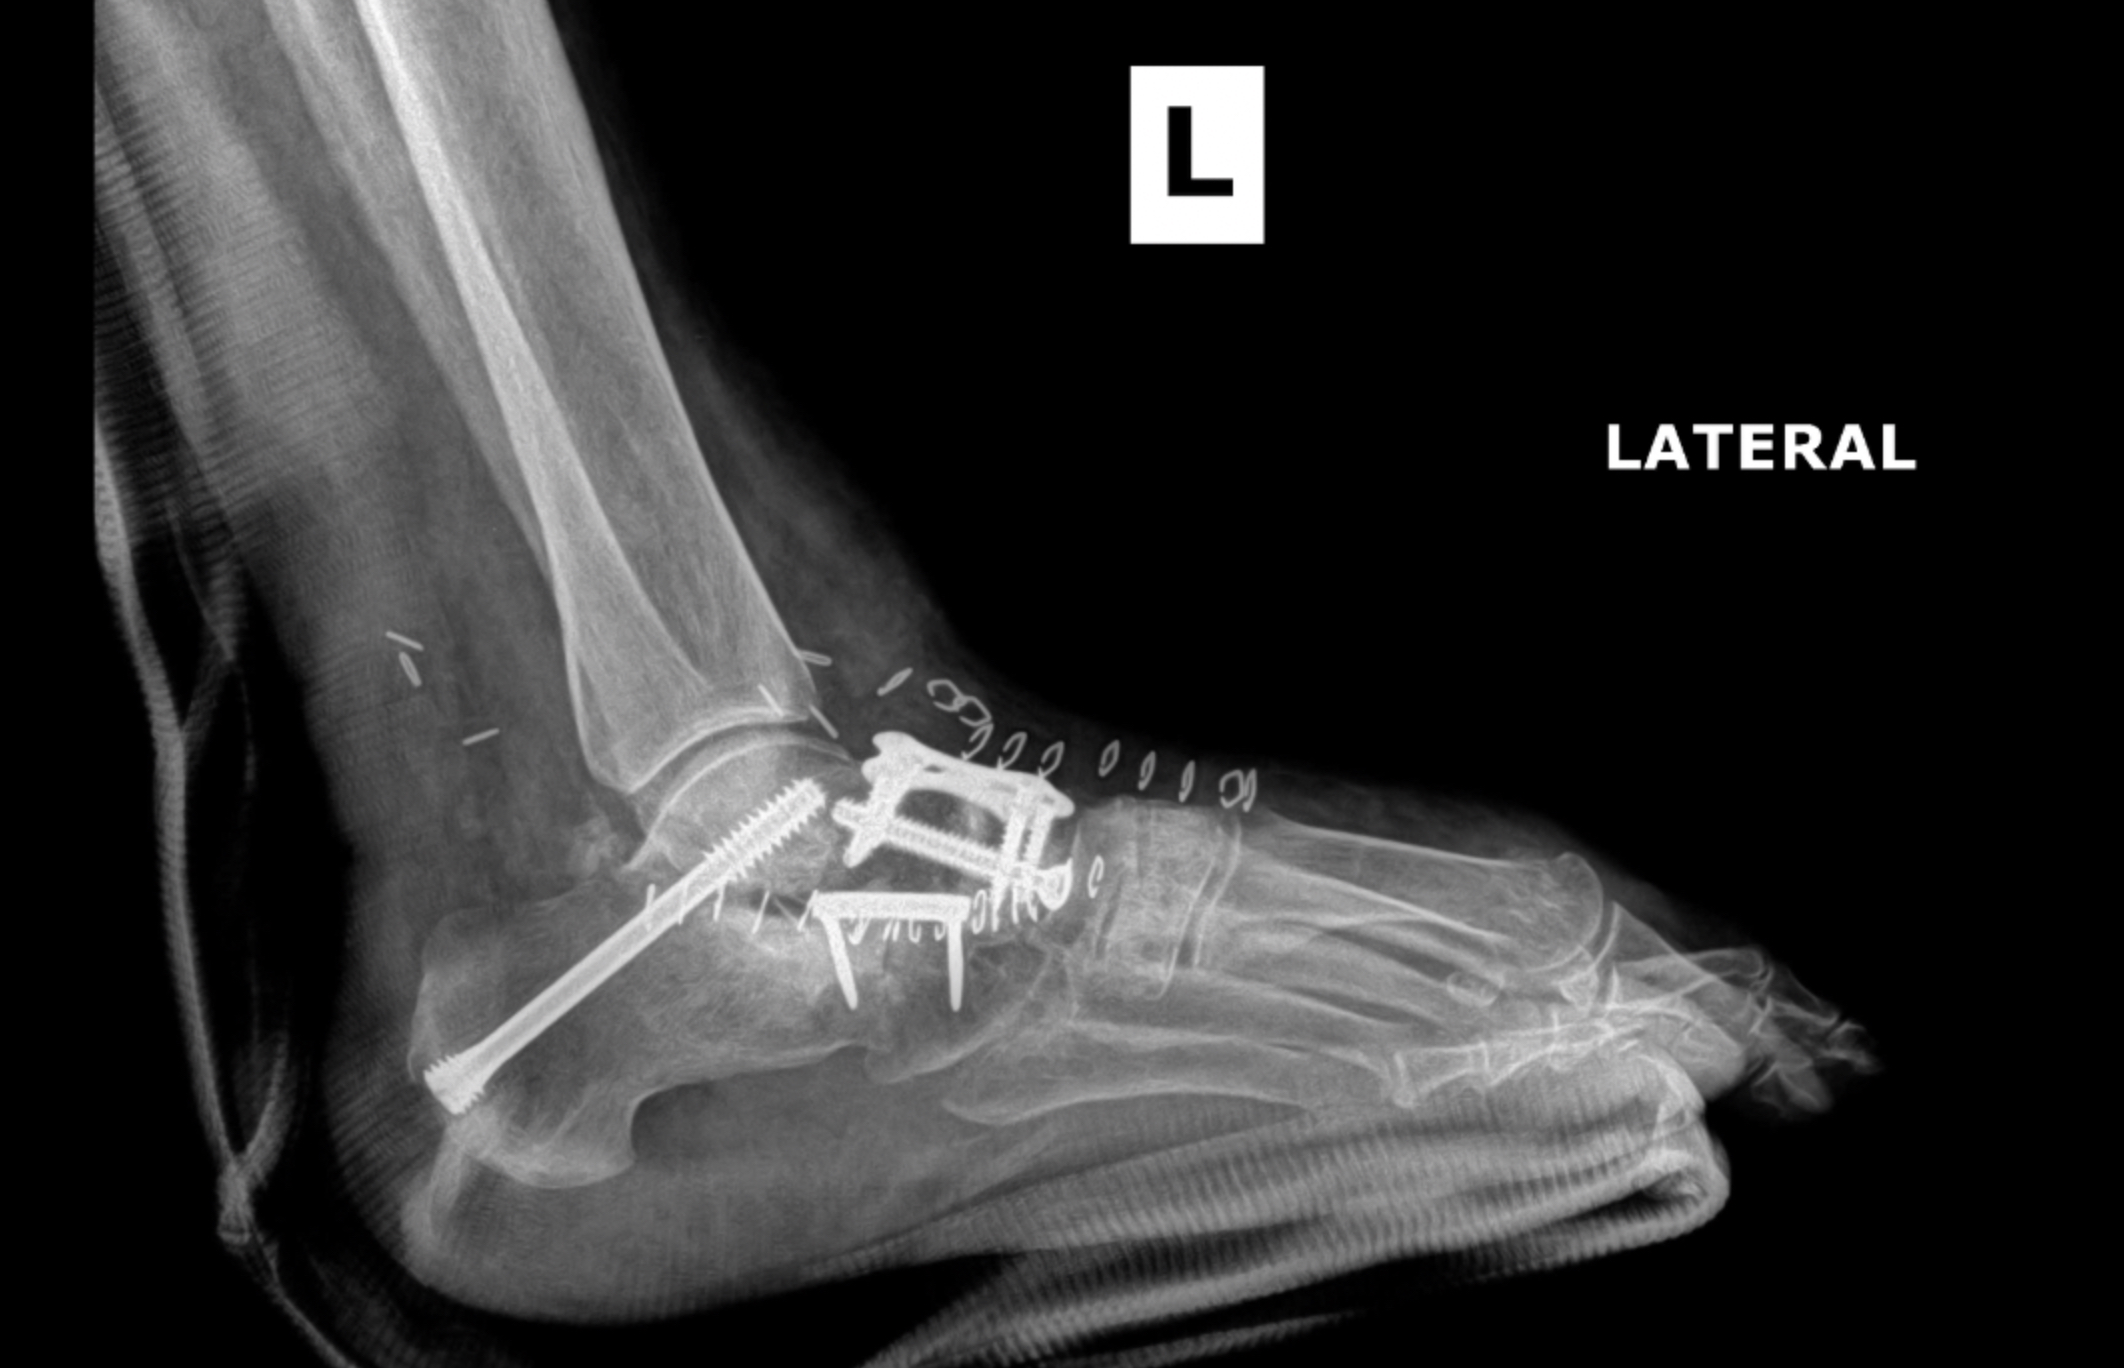

Postop XR Images